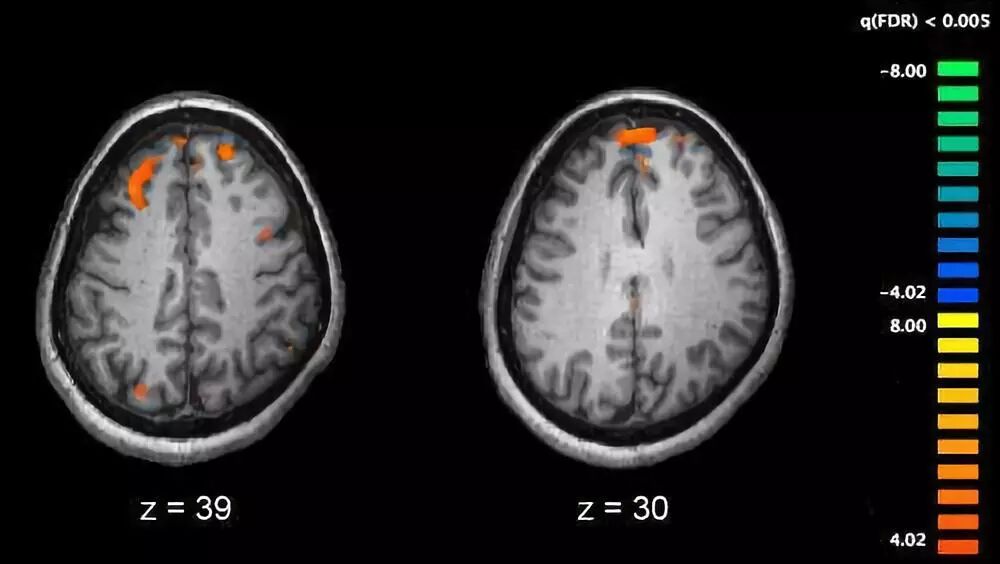

重新同步神经元可缓解精神分裂症

精神分裂症是一种使人衰退的严重神经发育障碍。找到与精神分裂症相关的电神经功能障碍和特殊的行为特点之间的因果关系是揭示这种疾病机制的关键所在。而近日来自瑞士日内瓦大学的研究人员在这方面取得了令人兴奋的进展,他们发现了导致神经网络去同步化的一种分子机制,并成功地修复了成年动物模型的这种组织缺陷,从而抑制了与精神分裂症相关的异常行为。

研究人员研究了人22q11删除综合征的一种动物模型,这种基因突变意味着发生精神分裂症的遗传风险最高。研究人员发现海马神经元聚集的非同步化是由于小清蛋白中间神经元兴奋性降低导致。通过药物或者遗传学手段恢复小清蛋白中间神经元的兴奋性就足以将成年动物的CA1网络动力学和依赖海马体的行为恢复至正常野生型动物的水平。

总的而言,这项研究为精神分裂症背后的神经网路功能异常的原因提供了新信息,表明在动物模型中逆转相关信号通路以恢复动物的生理活动和行为是可行的。